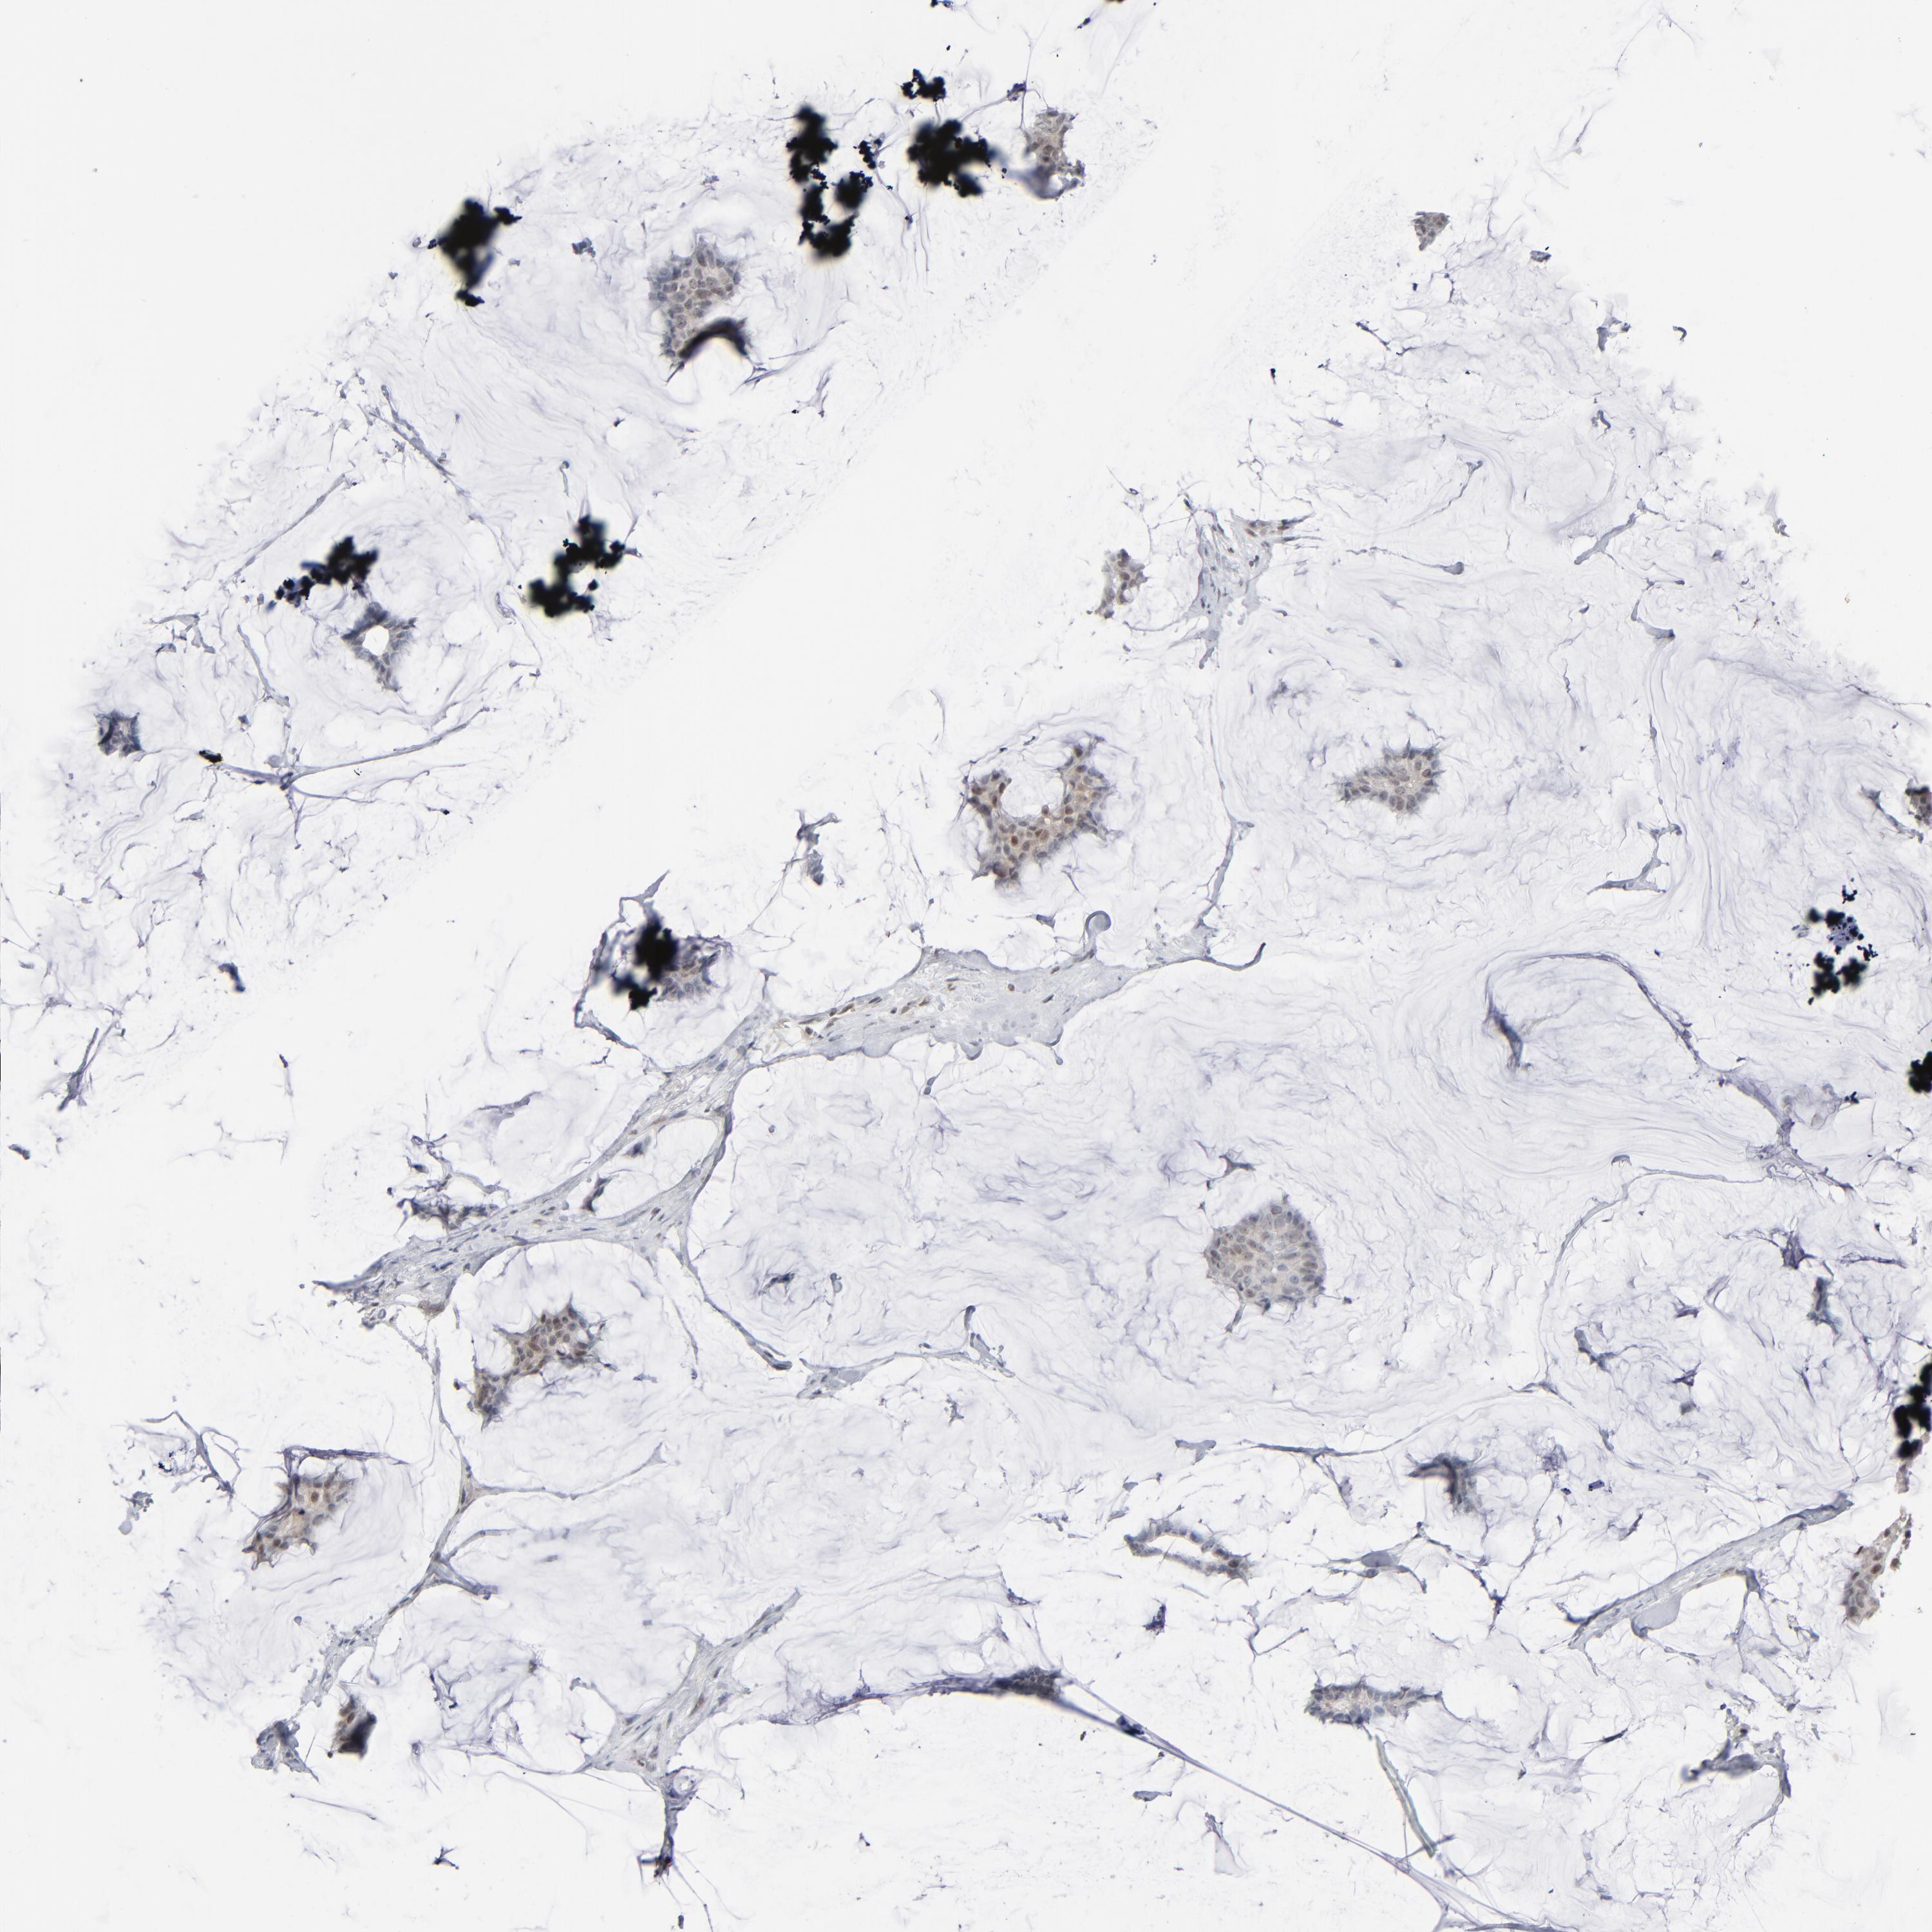

Breast cancer

Human cancer